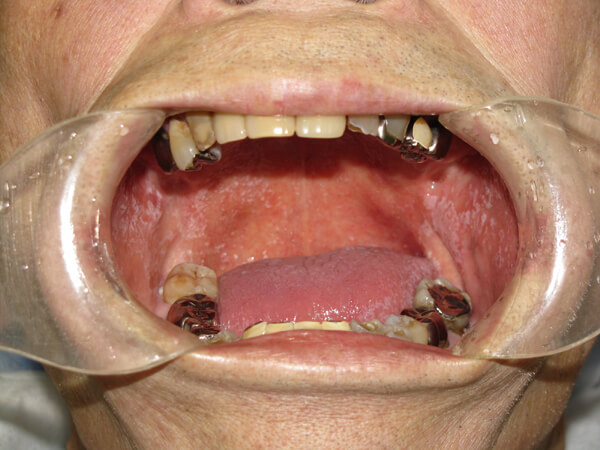

口腔粘膜疾患とは口の中の粘膜(舌、歯肉、口蓋、頬など)が、白色や赤色に変色したり、水疱(水ぶくれ)ができたり、表面の凸凹、不整な形、ヒリヒリした痛みがあるなど様々な兆候を示します。これらのなかには、良性、悪性、または悪性に変化する病気もあります。治療は、投薬、歯や義歯(入歯)の調整などをして経過を診るものから、変化した組織を採取して顕微鏡の検査を行う場合もあります。その結果によっては、病変部を切除することもあります。現在、かかりつけ歯科では、歯だけではなく、口の中全体をチェックしますので定期的に通院しましょう。また、変化があれば、すぐにご相談下さい。

口腔粘膜疾患の例